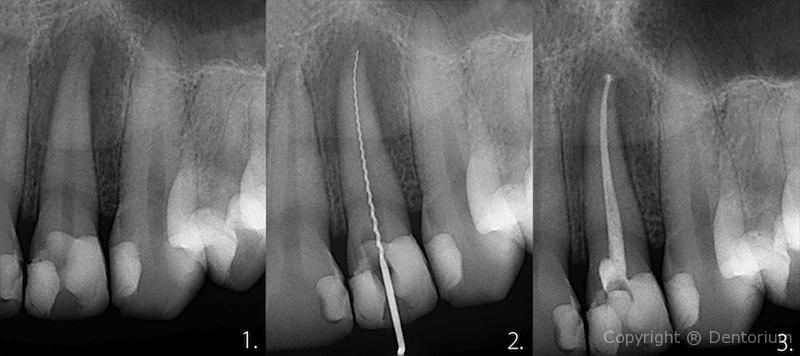

Il trattamento endodontico o trattamento canalare è necessario quando la polpa dentale è danneggiata dalle infezioni batteriche dalla carie o da trauma del dente.

- pulizia, allargamento e disinfezione del canale, somministrazione della medicina

- l’estrazione della medicina dentale, otturazione dei canali radicolari

- ricostruzione con il perno e otturazione dentale

Immediamente dopo il trattameneto si procede con RVG controllo del canale trattato.